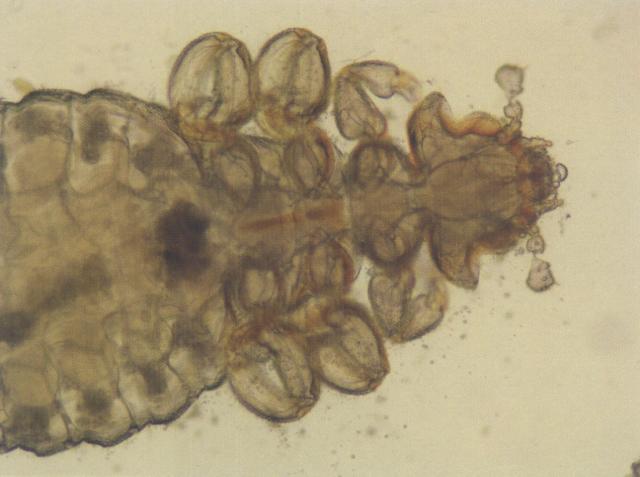

icon疥螨和疥螨的卵(犬,油法透明化,400×)

疥螨和疥螨的卵(犬,油法透明化,400×)

资源描述:疥螨科螨虫呈微黄白色圆形或龟形,背面隆起,腹面扁平且有四对足。犬疥螨体长不超过0.45毫米,猫背肛螨体长不超过0.25毫米,虫卵呈椭圆形,平均大小约150微米×100微米。

icon疥螨(犬,油法透明化,400×)

疥螨(犬,油法透明化,400×)

资源描述:疥螨(犬,油法透明化,400×)。疥螨科螨虫呈微黄白色圆形或龟形,背面隆起,腹面扁平且有四对足。犬疥螨体长不超过0.45毫米,猫背肛螨体长不超过0.25毫米,虫卵呈椭圆形,平均大小约150微米×100微米。

icon疥螨的卵(犬,油法透明化,400×)

疥螨的卵(犬,油法透明化,400×)

资源描述:2个疥螨的卵(犬,油法透明化)(400×)

雌雄螨在皮肤表面交配后,雌螨钻进宿主表皮深层挖掘虫道产卵,并以表皮深层的上皮细胞、组织液为食。